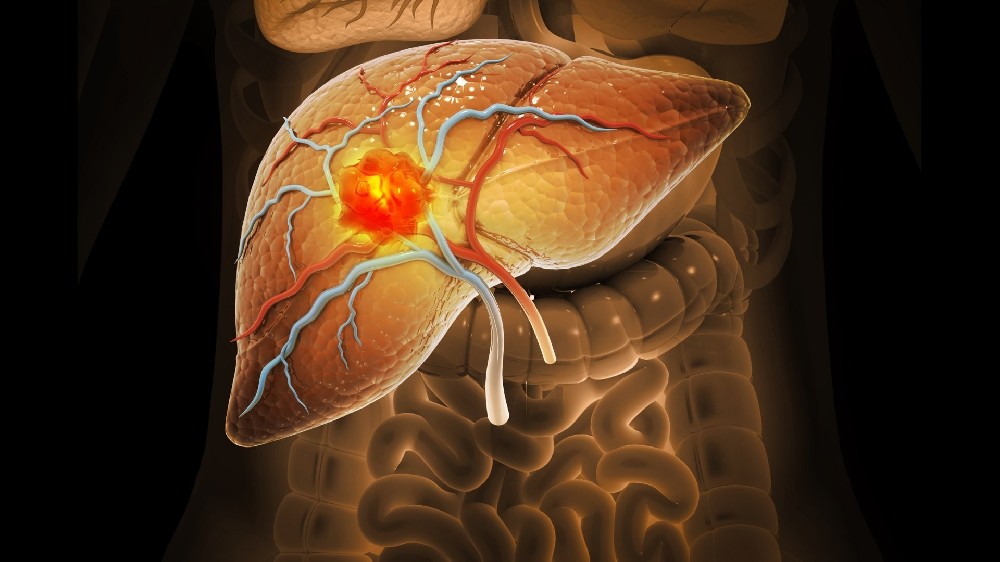

肝癌

經過 4D 的新陳代謝重新編程後 改良阿特金斯飲食 和精確的 Y90 放射栓塞治療肝臟腫瘤,我的腫瘤科醫生非常震驚:轉移灶消失了。團隊還利用樹突狀細胞疫苗優化了我的免疫反應 免疫 並使治療週期與我的睡眠覺醒節律同步。我已經兩年沒有罹患癌症,而且每週都會去爬龍背山!

吳女士,52 歲

大腸癌